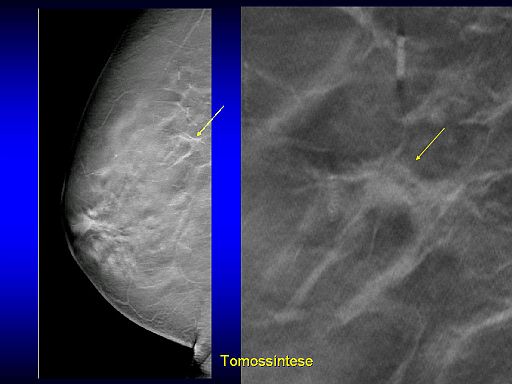

Entra em operação o primeiro equipamento de tomossíntese do país. Recentemente apresentado na Jornada Paulista de Radiologia, a mamografia em 3D elimina a superposição de tecidos, melhora a visualização dos contornos das lesões e aumenta entre 10% e 15% a detecção da doença, de acordo com estudos iniciais.

Na opinião de Aron Belfer, em termos de tecnologia, a mamografia digital 2D é um avanço importante em relação à mamografia analógica, convencional. Já a tomossíntese, de acordo com estudos recentes, surge como uma tecnologia capaz de detectar lesões que antes passariam despercebidas na mamografia digital 2D. “A detecção de tumores menores permite recorrer a cirurgias menos mutilantes, resulta em menor custo global do tratamento, maior sobrevida e melhor qualidade de vida das pacientes”.